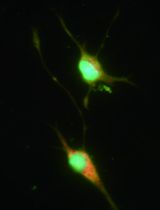

A population of muscle resident CD45-, CD31- cells expressing the mesenchymal PDGF receptor alpha (PDGFRα) as well as Sca-1 was first isolated in healthy mouse muscles in Uezumi et al. (2010). In the same year, Joe et al. (2010) identified and purified fibro-adipogenic precursors (FAPs), cells located into the interstitial space between myofibers close to vessels, negative for CD45, CD31,α7-Integrin, but expressing CD34, Sca-1.

FAPs are an important source of fibrosis and adipogenesis in dystrophic skeletal muscle (Natarajan et al., 2010; Cordani et al., 2014). We have recently demonstrated that Nitric Oxide regulates FAP fate inhibiting in vitro their differentiation into adipocytes. In mdx mice, an animal model of DMD, fed with a diet containing the nitric oxide donating drug, Molsidomine, the number of PDGFRα+ cells was reduced as well as the deposition of both skeletal muscle fat and connective tissues (Cordani et al., 2014). Here we described a method to isolate in both wild type and in mdx dystrophic muscle pure population of FAPs by double selection for SCA-1 and PDGFRα positivity in absence of the satellite cell markers SM/C2.6 and α7integrin as well of the pan-lymphocytes marker CD45 or endothelial marker CD31.